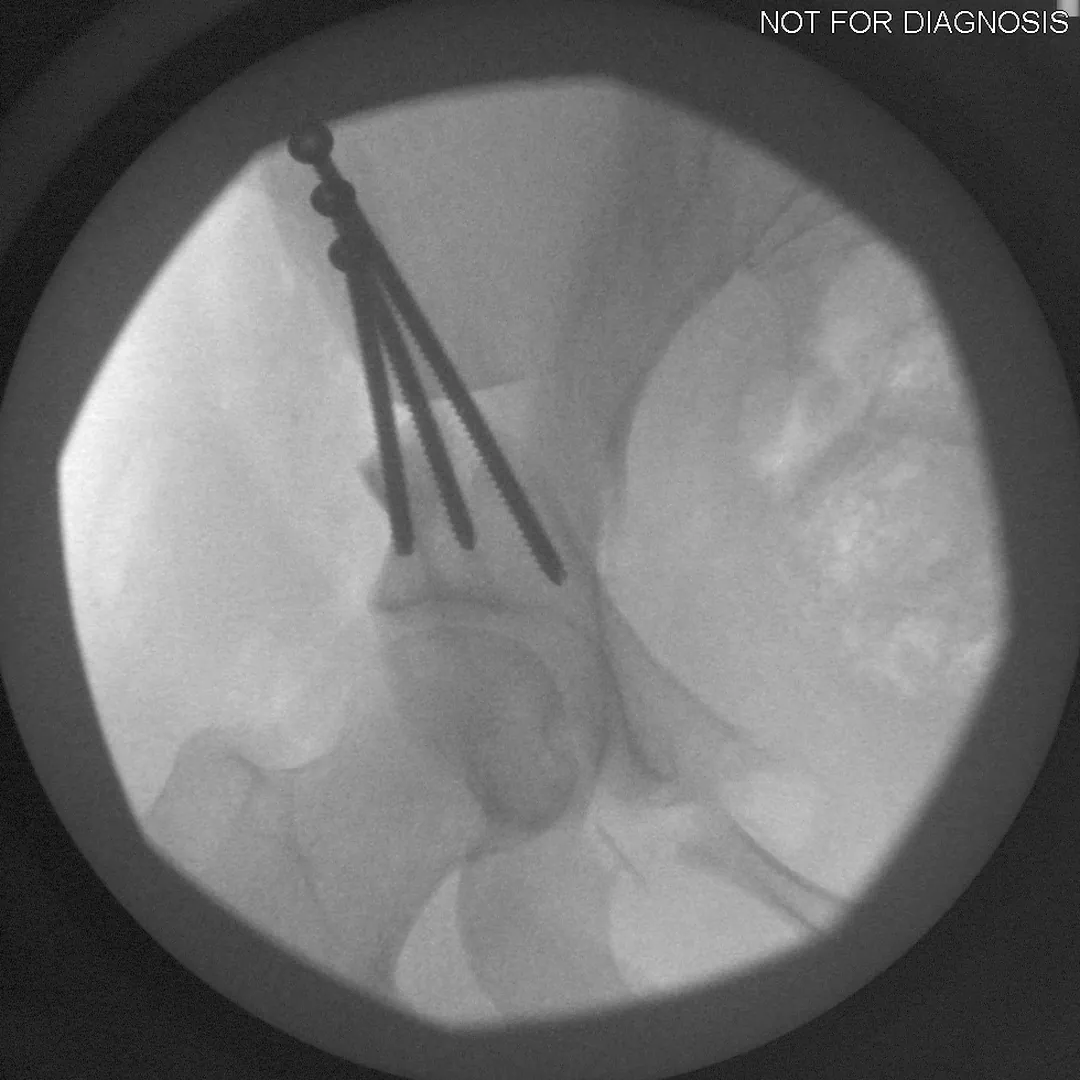

During a PAO, the surgeon carefully cuts the bone around the hip socket and repositions it to provide better coverage of the femoral head. The socket is then fixed in its new position using screws. The goal is to improve hip stability, reduce pain, and preserve the patient’s natural hip joint.

• Screws shown securing the acetabulum in its new position

• Several controlled bone cuts are made around the hip socket

• The socket is repositioned and fixed with screws

• The hip joint itself is preserved